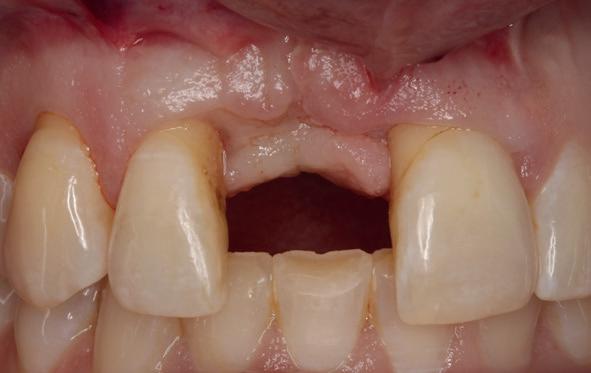

Implantologische behandelingen in het esthetische front vragen meer dan technische vaardigheid alleen. Ze vragen om overzicht, timing, vertrouwen en een team dat als vanzelf samenwerkt onder druk. Juist bij complexe casussen, waarin angst, infectie en hoge esthetische verwachtingen samenkomen, wordt zichtbaar hoe bepalend de rol van de tandartsassistent is.

Deze casus beschrijft een uitgebreide immediate implantaatbehandeling bij een patiënt die door meerdere collega’s werd geweigerd. Niet omdat de mogelijkheden ontbraken, maar omdat de complexiteit vroeg om een perfect afgestemde samenwerking. Het verhaal laat zien hoe de assistent in zo’n traject veel meer is dan een uitvoerende kracht of “mal”, maar een dynamische surgical guide die het proces mede stuurt, bewaakt en mogelijk maakt.De patiënt: wanneer alles samenkomt

Ze kwam binnen op een dinsdagochtend, iets voor achten. Een vrouw van begin zeventig, met een zachte stem en ogen die meer vertelden dan haar woorden. Ze vertelde dat ze een eigen B&B had en dat ze zich nauwelijks kon voorstellen gasten te ontvangen zonder tanden. Op dit moment kon ze echter nauwelijks lachen. “Het doet pijn… en het ruikt soms ook niet goed,” zei ze bijna verontschuldigend. Haar oude bovenbrug, die ze al meer dan twintig jaar droeg, was langzaam maar zeker ingestort. Er was sprake van cariës onder meerdere pijlers, pusafvloed,

chronische ontsteking en een brug die mobiel was en elke beet pijnlijk maakte. Ze had inmiddels meerdere tandartsen bezocht. Drie hadden haar geweigerd. Te complex. Te veel wensen. Te onvoorspelbaar.

De kern van haar vraag was eenvoudig en tegelijkertijd uitdagend: Is het mogelijk om mijn huidige brug te dupliceren en een nieuwe brug te vervaardigen met minder complicaties?

De basis van een complexe beslissing

Mijn behandelplan begint altijd met een uitgebreid klinisch onderzoek. Dat omvat een medische anamnese, intra- en extra-orale camerafoto’s en uitgebreid verwachtingsmanagement. In deze fase is mijn assistent vooral bezig met het zorgvuldig vastleggen van alle gegevens. Juist dat nauwkeurig documenteren zorgt voor rust in de behandelkamer. Minstens zo belangrijk is het luisteren naar de patiënt. Niet alleen naar de klachten, maar naar het

1. Extra-orale foto (lachlijn).

2. Beoordeling van zacht weefsel en botcontour.

3. Reflectiefoto – beoordeling van occlusievlakken en tandboog.

4. Pre-chirurgische OPG.

levensverhaal en de mens achter de brug. Begrijpen wat deze behandeling voor iemand betekent, is cruciaal voor het uiteindelijke succes.

Na het klinische onderzoek volgde het röntgenologisch traject. De CBCT liet precies zien wat we al vreesden: een front waarin het bot onregelmatig was, duidelijke radiolucenties rond de pijlers en een infectiegebied dat zich onder vrijwel de gehele brug had verspreid. Tegelijkertijd was er ook potentie. Net voldoende botstructuur om immediate implantaatplaatsing te overwegen, mits alles perfect gepland zou worden.